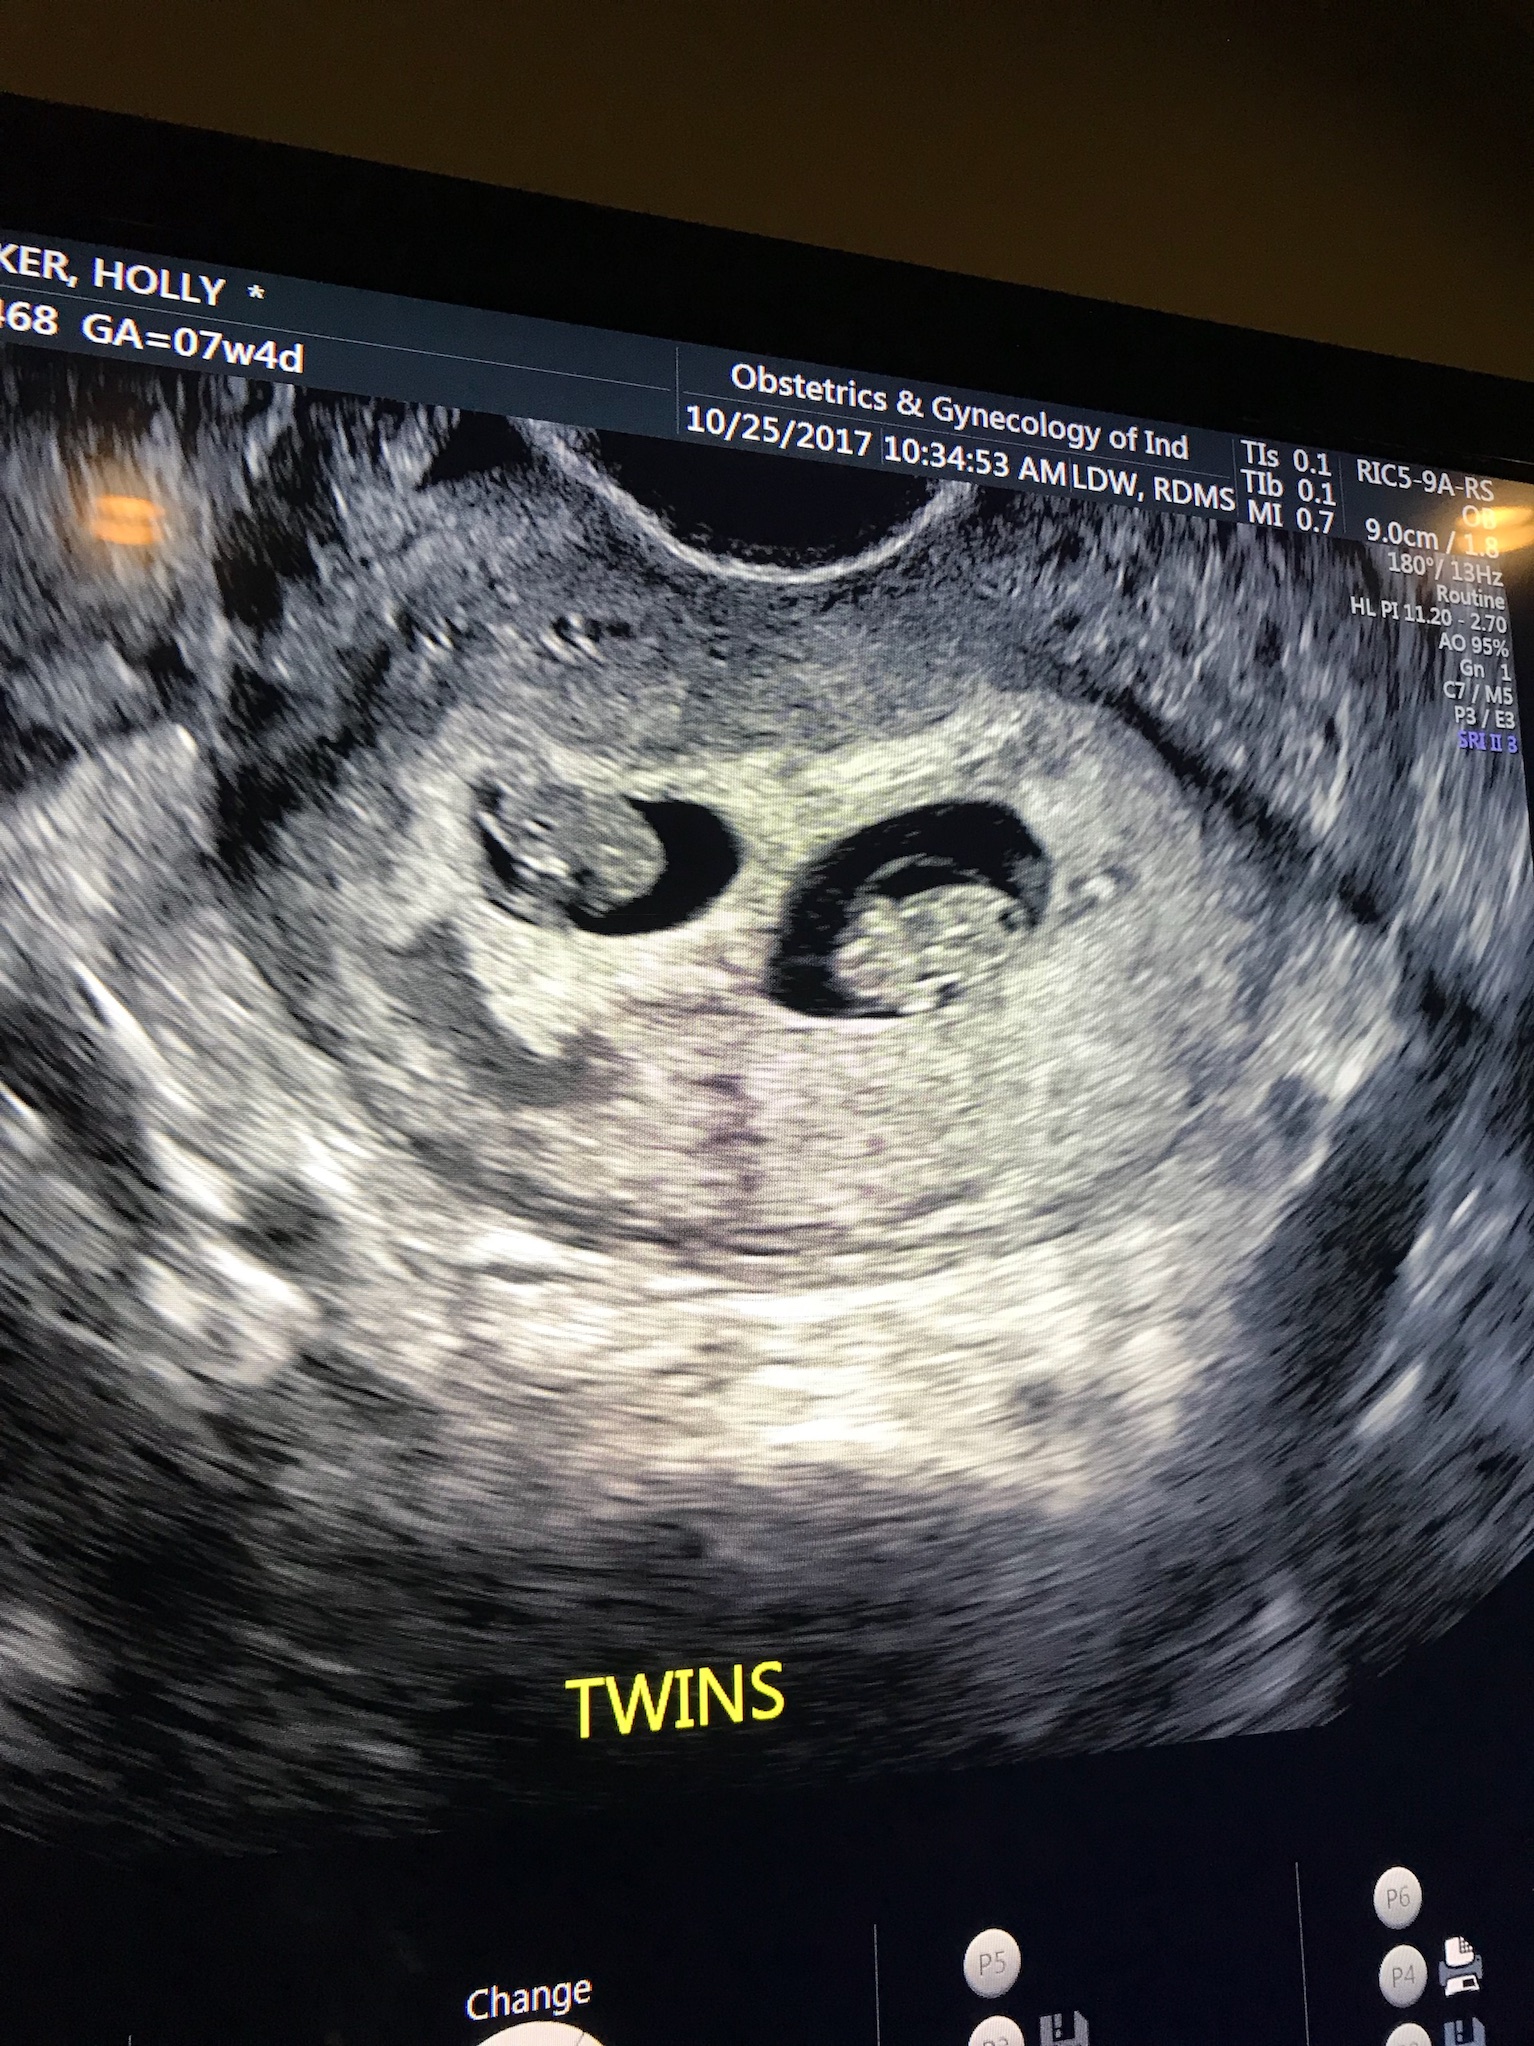

I always knew I wanted to be a mother. I always have known I wanted a big family. My dream has always been to have children. I wanted the picture perfect layout of life. Find an amazing man, get engaged, have a fairy tale wedding (totally did–that’s a whole other post), and then start a family. Just over 3 months into my marriage, I found out I was pregnant. We were so excited, but also a little terrified of what was to come (normal right?). Anxiously awaiting the coming couple of weeks before we had our first ultrasound, we told our closest family and friends (we could not keep that secret), by sending them a little picture of some alfredo & pregnancy test. At my eight week ultrasound, we were excited to see our little gummy bear of a baby, and hear the heartbeat. We were filled with nerves when the ultrasound tech said, “Wait a minute…” Umm.. WHAT. Never tell an expecting momma to “wait” without telling her why. It was a few minutes (felt like an hours) that passed when she asked if twins ran in my family… “No… WHY?” Because she found Baby A, and a Baby B. My eyes swelled with tears (excitement, fear, a little… What the HECK?!). Adam was beaming with happiness. Our amazing doctor, told us we had two very strong heartbeats, and to prepare for a life with twin babies. We left that ultrasound with a whole new expectation of this pregnancy. The coming weeks I did everything I was supposed to do as an expecting momma– ate all the right foods, took my prenatal and folic acid, plenty of sleep, etc. We were excited to see our sweet babies at our next ultrasound at 12 weeks. At the routine appointment, we were shocked to see that there was no growth in Baby A. There also was no heartbeat. Devastation was an understatement. I felt like I had failed as a mother… “What did I do wrong??” was all I thought… I felt no physical pain, no bleeding, nothing out of the “norm.” How could this of happened??? I couldn’t even look at the screen due to being so upset about having lost one of my babies… (Que guilt of not “caring” about the other healthy baby that was THRIVING). My emotions had complete control of me. I was in a whirlwind… So upset over having lost my baby, but felt lucky that I still had a healthy baby thriving inside. I can’t even imagine the pain, the horror, the guilt of if I had lost both. My heart still sinks when reliving that day, and even thinking about the thousands and thousands of mommas who have gone through miscarriage. There was no explanation as to why this happened other than it was probably just a chromosomal disfunction or one of the babies (Baby B) was taking more nutrients than the other. That was hard for me to swallow.. the WHY. After my grief period, I picked myself up and was able to thank God for giving me the opportunity to still nurture the strong baby I still had. I decided that there was a greater reasoning behind the “WHY,” and I was going to “give it to God.”